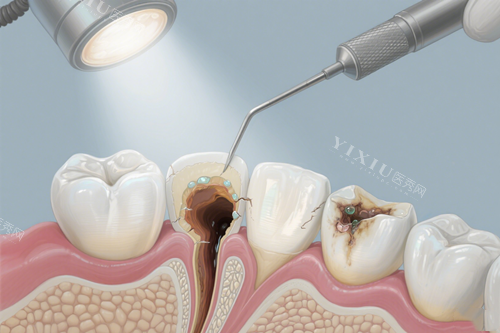

给我看病的是一位经验充足的医生,他先是仔细地询问了我的症状,然后让我去拍了个牙片。拍完牙片回来,医生给我分析了牙齿的情况,说我的牙神经已经发炎了,需要做根管治疗。我一听有点害怕,之前也听说过根管治疗挺疼的,就问医生会不会很疼。医生耐心地跟我解释,现在的技术很靠前,治疗过程中会打麻药,不会让我有太多痛苦的,让我别担心。

在根管治疗的过程中,要分好几次去医院。头一次主要是开髓引流,减轻牙齿的压力,减弱疼感。第二次是清理根管,把里面的感染物质都清除干净。这一步有点麻烦,医生特别细心,清理得很干净。第三次就是填充根管了,填充完之后,牙齿就不会再疼了。每次去医院,医生都会详细地跟我说下一步的治疗方案,让我心里有底。